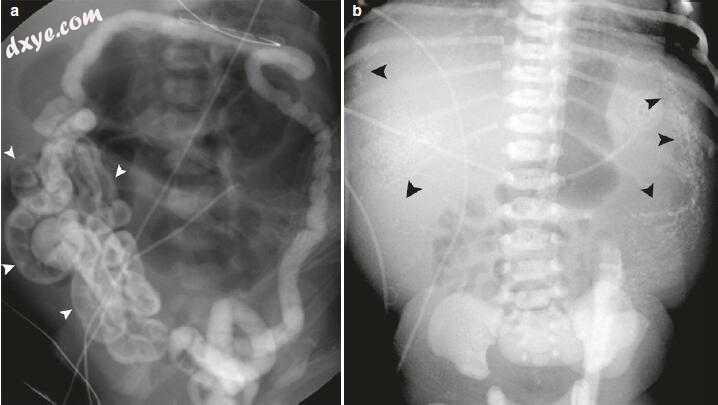

图15.4回肠闭锁被认为是由子宫内的肠系膜血管事件引起的。 (a)有回肠闭锁的新生儿的X光照片显示整个腹部有多个肠袢扩张,表明阻塞较低。 (b)同样的荧光镜造影剂灌肠

儿童表现出典型的“微管”(未使用的结肠)和未扩张的远端回肠的逆向填充至闭锁水平(箭头)。 更近端的肠袢扩张并充满空气